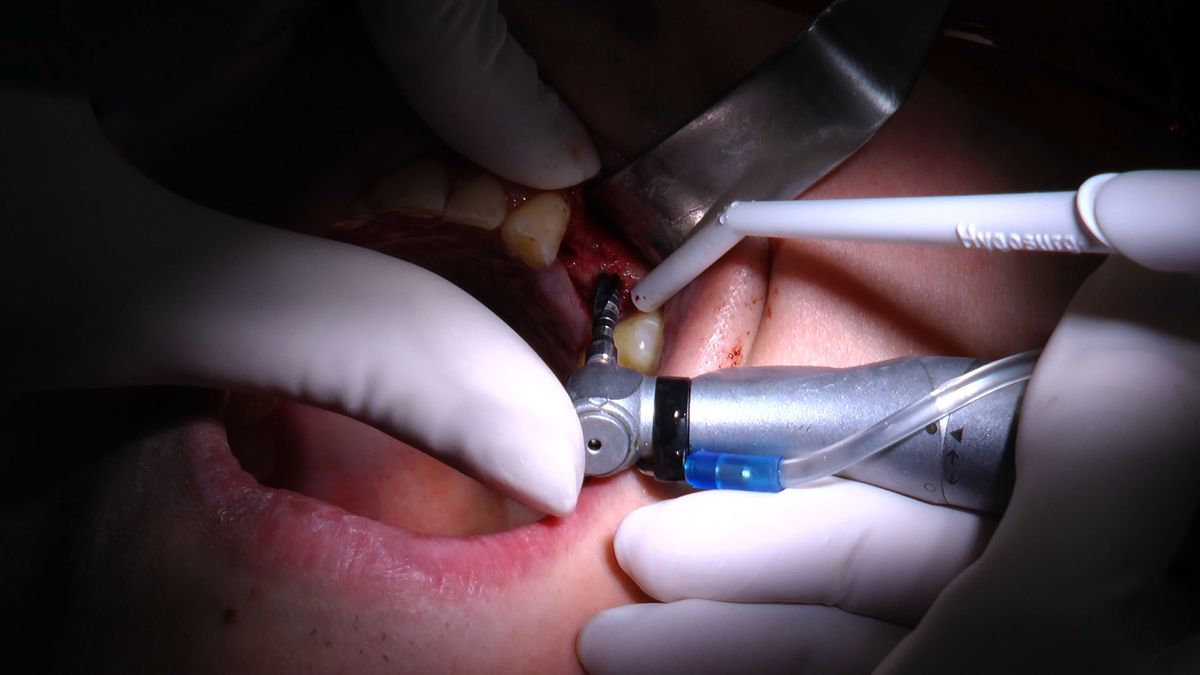

Pierwszy weekend 2019 roku w Instytucie Vivadental, to doskonałe otwarcie kolejnego roku edukacyjnego i szkolenia naszych Kursantów. W drodze do sukcesu w implantologii zdobywają wiedzę i umiejętności, a każdy kolejny zabieg to impuls i inspiracja do twórczego rozwoju w leczeniu własnych Pacjentów. Rozpoczęliśmy od sesji praktycznej implantologicznej właśnie z udziałem Pacjentów, na której dominowały samodzielne zabiegi wykonywane pod kierunkiem Mentorów – dr n.med. Violetty Szycik i dr n.med. Magdaleny Kisłowskiej – Syryczyńskiej. W ciągu dwóch dni zabiegowych przyjęliśmy 14 Pacjentów, przeprowadziliśmy zabiegi chirurgiczne, zabiegi regeneracyjne tkanki kostnej i augmentacji oraz wszczepiliśmy 20 implantów systemu Axiom. W ramach panelu edukacyjnego Sukces Twojego Biznesu odbyły się kolejne zajęcia z NLP, na których nasz Mentor Mariusz Wójcik z Gdańskiej Akademii Umiejętności Menedżerskich, kontynuował wprowadzenie do psychologii i podstaw kierujących decyzjami Pacjentów. Ćwiczenia w wesołej i koleżeńskiej atmosferze były niezwykle pouczające, a jednocześnie stanowiły idealną odskocznię po wyczerpujących zabiegach.